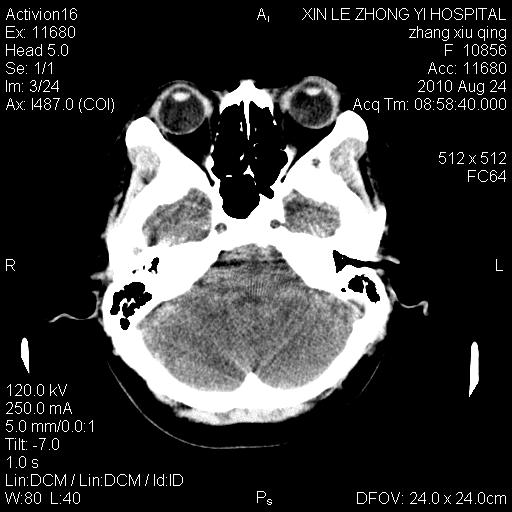

标题: CT28569:看看鞍上池正常吗 [打印本页]

标题: CT28569:看看鞍上池正常吗

女 24 偶有头晕

怎么这么多伪影?我感觉没什么特别异常哦,是不是伪影所至呀

病史?感觉有水肿,炎症或转移

伪影多,建议行mri!

未见明显异常,必要时可作mri

没什么!只是扫描层面与听眦线不平行

伪影干扰下,所见无水肿、无占位,建议定期复查。